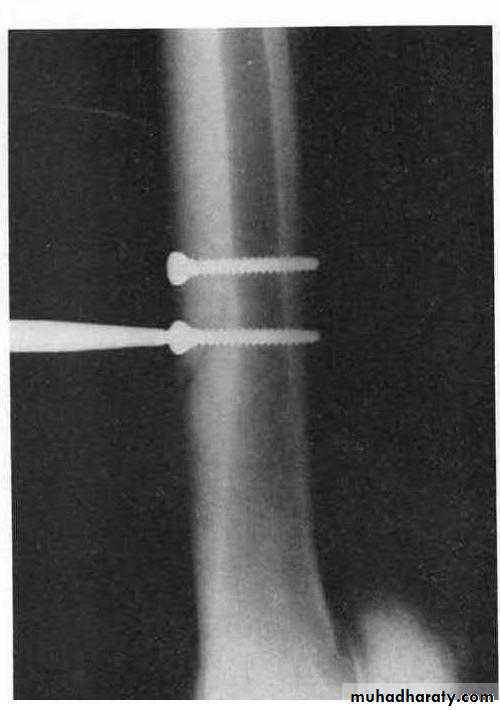

Surgical procedure by internal fixation of the fracture either with transcortical or unicortical method using bone screw. Avoids placing the screw close enough to the second metacarpal bone that it may cause irritation or deviation of it.

Upper, Illustrates the transcortical method. Lower, Illustrates unicortical method.

Two screws placed transcortically are used to repair saucer fracture.Splints